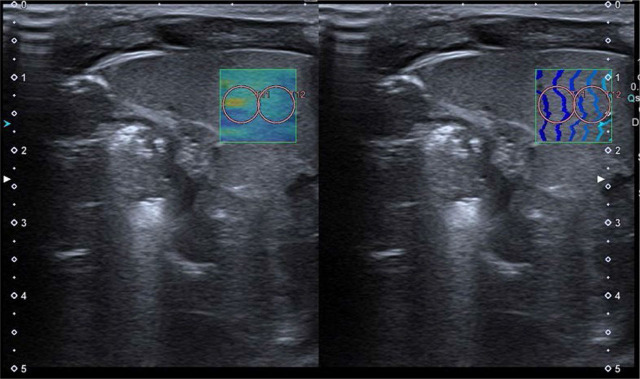

Materials and methods: We performed two-dimensional shear wave elastography of the liver, spleen and kidneys using a linear transducer at least 60 minutes after food intake in a group of 58 healthy, full-term, spontaneously breathing newborns. A series of 5 measurements using 5-mm-diameter regions of interest were performed, with the results expressed in m/s and kPa. Exam feasibility was assessed using the IQR/Median ratio as ≤30% for kPa, and ≤15% for m/s. Descriptive statistics, Shapiro-Wilk W, Levene's, Mann-Whitney U tests and Spearman correlation analysis were used for statistical assessment.

Abstract Image